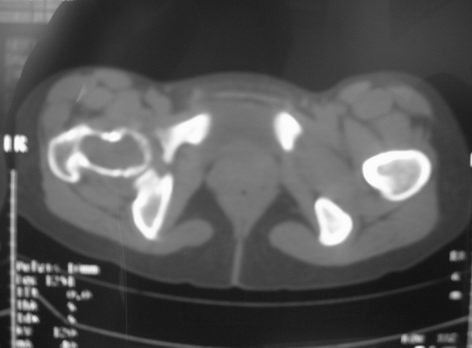

右股骨骨巨细胞瘤

女,31岁,右髋部疼痛半年,加剧两天不能行走

杀毒软件发言:囊状透亮区,纵行发展,边轻度硬化,碎片陷落征。

dyqct发言:支持右股骨头、颈骨巨细胞瘤可能性大(跨越骺线).